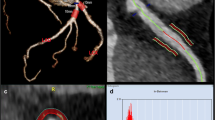

After curing, the hearts were placed inside cylindrical radiolucent plastic containers and expanded polystyrene beads were used to fill the surrounding volume as shown in Fig. 1a, b. The preparation was reproducible and constituted a clean and easy-to-handle ex vivo heart phantom with contrast-enriched coronaries as demonstrated in Fig. 1c.

Experimental set-up and image analysis. a Schematic representation of the experimental set-up showing the hearts positioned to resemble a pyramidal stack: top row (centered position, T), left bottom row (L), and right bottom row (R). b Arrangement of three porcine hearts in containers used for imaging. c CT short-axis view of the porcine heart. The LV and the coronary arteries are filled with 1% agar-agar and 9 g/mL iodine solution. d1 Volume of interest in a transaxial view of the LAD. The blue outline indicates the vessel lumen while the green one marks the surrounding volume evaluated for PCAT attenuation. d2 PCAT phenotyping in transaxial view. The heatmap corresponds to the established HU range of adipose tissue (d2). Abbreviations: CT, computed tomography; HU, Hounsfield unit; L, left; LAD, left anterior descending artery; LV, left ventricle; PCAT, pericoronary adipose tissue; R, right; RCA, right coronary artery; RV, right ventricle: T, top

PCAT attenuation measurements were performed using a semi-automated workflow in PMOD 4.203 (PMOD Technologies LLC). All visible coronary arteries were manually traced starting at their origin for up to 40 mm or for the total length available by using the images acquired at 120 kVp and reconstructed with IR. The tissue within a radial distance from the artery equal to the vessel diameter was considered perivascular adipose tissue returning a tube-like 3-dimensional (3D) volume of interest (VOI) along each vessel, as previously reported [3, 7]. Within this 3D VOI, the adipose tissue was defined as all voxels with an attenuation ranging between − 190 and − 30 HU, as demonstrated in Fig. 1d1, d2. The 3D VOI obtained from the 120-kVp images was then transferred to all remaining co-registered datasets acquired at 80, 100, and 140 kVp, and the PCAT mean attenuation (PCATMA) was calculated.